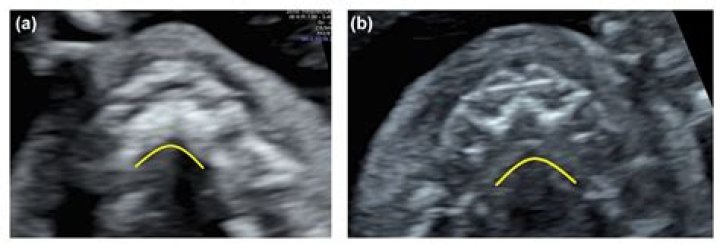

Prenatal Diagnosis of Cleft Palate